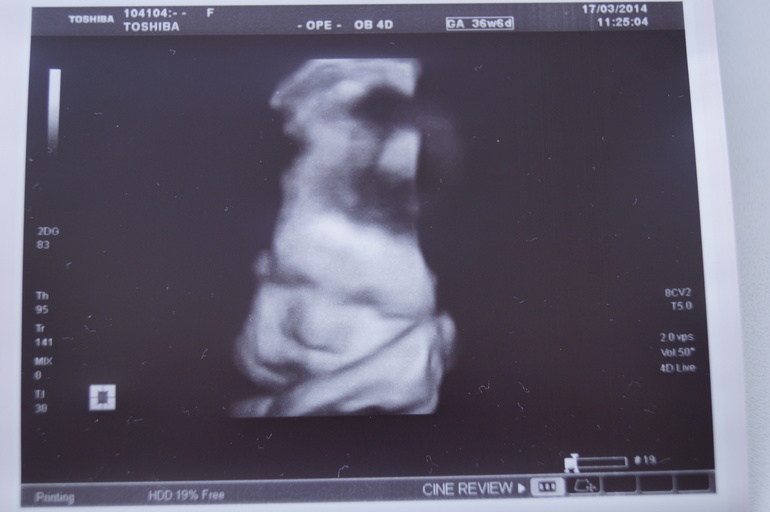

Наш хомячок))))

И в первом и во втором результате узи вроде бы всё нормально. Всё в норме и без патологий. Но в сегодняшнем узи меня поднапрягла фраза о многоводии. Всю беременность воды были в норме. Смотрела по таблицам в инете для срока в 36,6 недель количество околоплодных вод может варьироваться от 66 до 275 мм. А у меня 83 мм. Неужели многоводие? Может врач ошиблась с этим диагнозом? Сегодняшнее узи по фетометрическим показателям ставит мне срок больше, чем врач. Узистка говорит, что мы готовы к рождению. По приходу домой я заметила, что пузик начал опускаться. И по-моему, даже начала пробка выходить. Немножко. К врачу на приём 24 числа. Анализы все хорошие и кровь и все анализы мочи. Мог ли врач-узист ошибиться с многоводием? И в последний раз я решила сделать 3 d узи. Теперь уж только вживую увидим нашу мышку. Думала мышка будет, а оказалось, хомячок. Щёчки пухлые. )))) Спала на узи с открытым ротиком и под головку ручку подложила. Так ведь помягче будет...))))

Наша хомяшка )))) . Ночью я сегодня плохо спала. Начала разваливаться. Правильно девочки говорят, то лапы ломит, то хвост отваливается. Теперь и я такая же развалюшка. )))) Но я не жалуюсь. Я всё вытерплю. Лишь бы малышке было хорошо и комфортно. Пусть вылупляется тогда, когда посчитает нужным!!!!